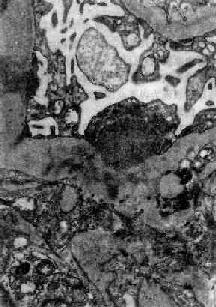

图12-8 毛细血管内增生性肾小球肾炎

电镜下见肾小球毛细血管基底膜表面上皮细胞下有多数驼峰状电子致密沉积物

图12-9 毛细血管内增生性肾小球肾炎

电镜下见驼峰状沉积物位于毛细血管基底膜表面。沉积物表面有上皮细胞覆盖,上皮细胞足突消失

在电子显微镜下可见肾小球系膜细胞和内皮细胞增生肿胀。基底膜和脏层上皮细胞间有致密物质沉积。这些沉积物大小不等,有的很大,在基底膜表面呈驼峰状或小丘状(图12-8,图12-9)。沉积物表面的上皮细胞足突多消失。基底膜变化不明显有时边缘稍不规则。沉积物一般在发病后几天就可出现,在4~6周内消失。有时基底膜内侧内皮细胞下和系膜内也可见小型沉积物。